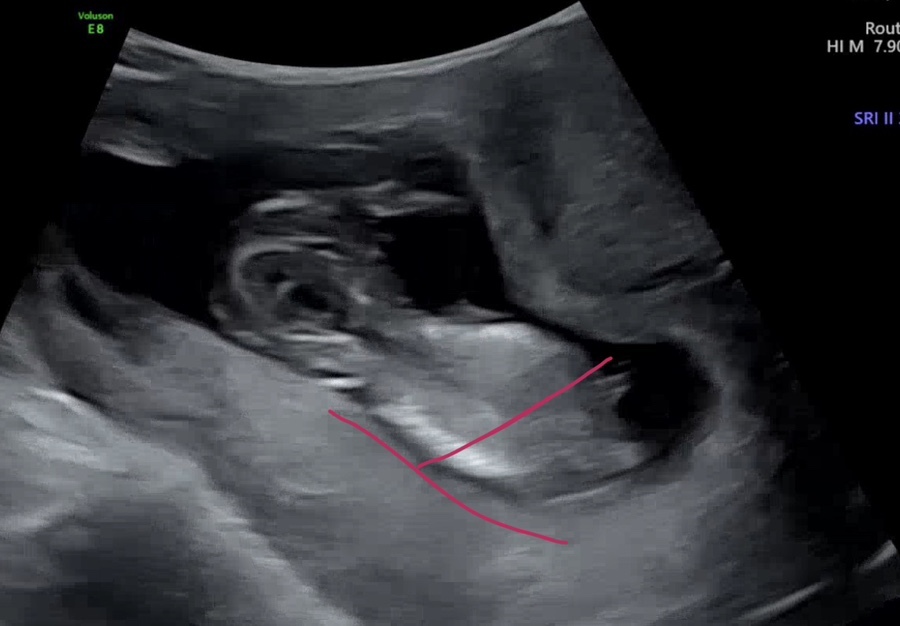

우리 첫째는~ 13주였을 때인데요? (아래사진)

저 빨간 부분 밑에 우리 아이의 소중이가 잘 보이지 않소이까… 난 하도 영상을 보다 보니까 보면 잘 보인다.

(맘카페에서 하도 많이 봤는데, 진짜 어쩔 때는 잘 안 보인다!)